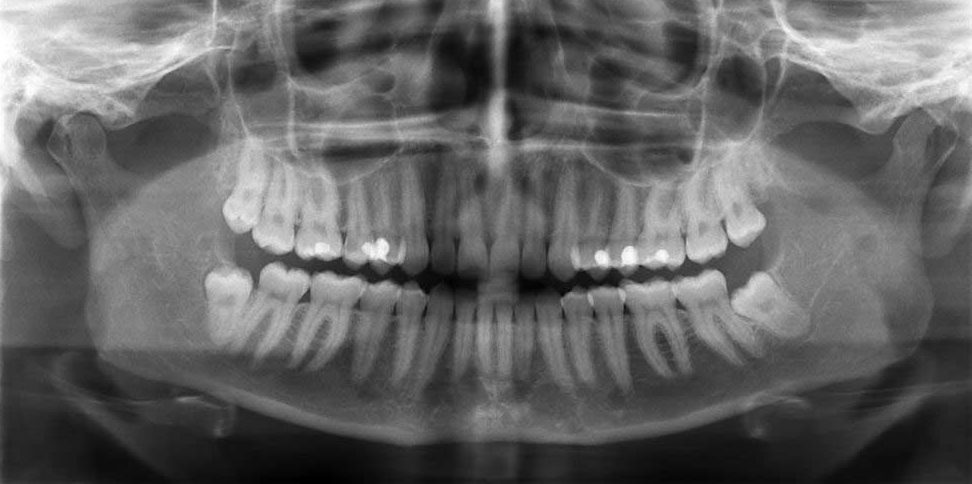

Cone Beam Computed Tomography (CBCT) is the most advanced type of dental x-ray and is available in very few clinics. The image produced is in 3 dimensions. In the above example, it is used in the precise planning of implant placement.